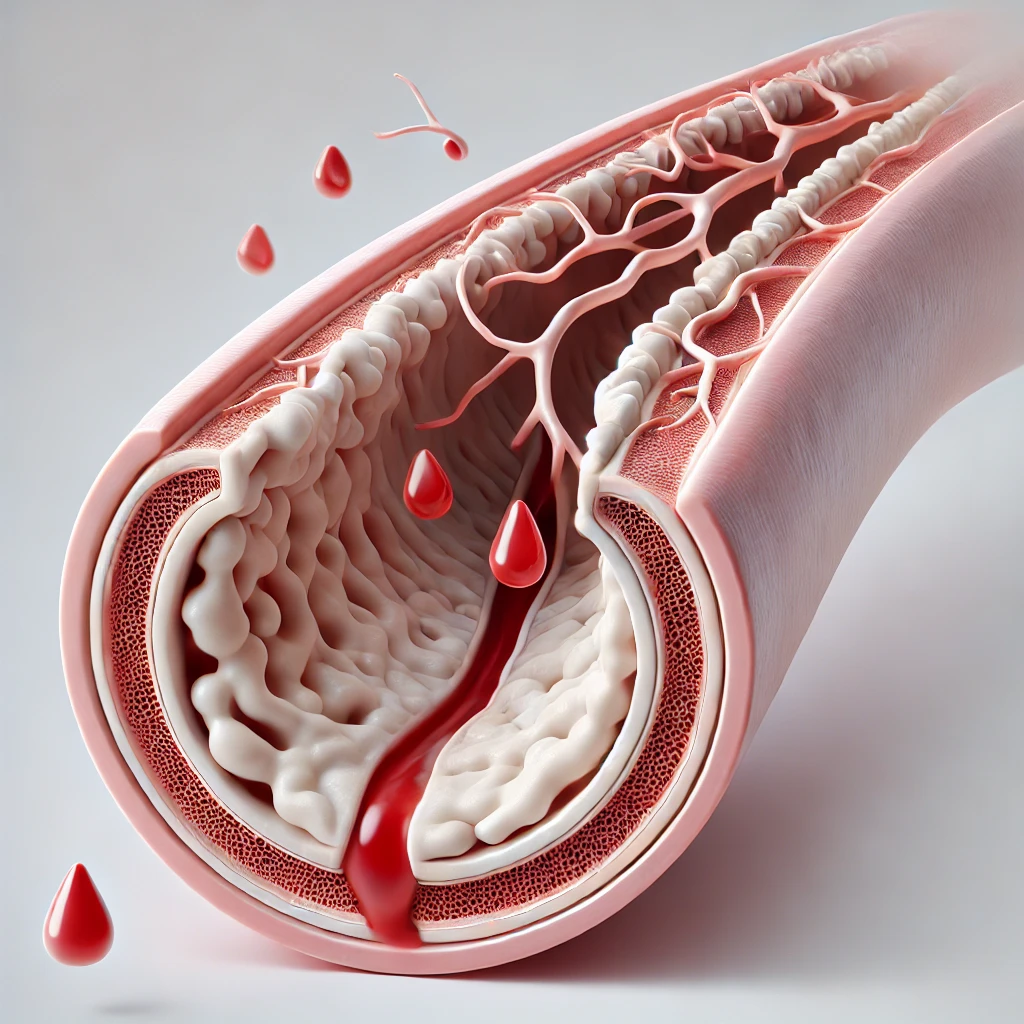

مقالات طبية من مساهمات الأطباء